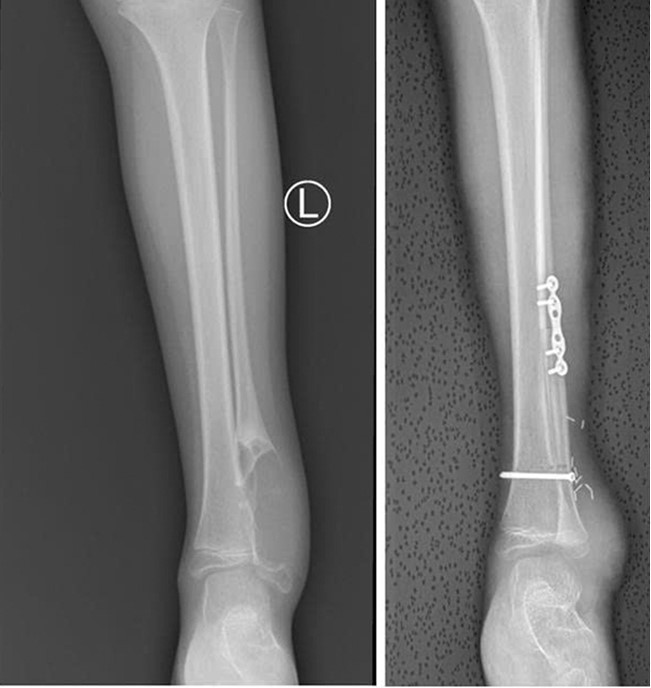

Hình ảnh X quang:(A) trước mổ cắt u, (B) sau mổ ghép vạt xương.

Sau mổ, trẻ hồi phục tốt, vạt da hồng ấm, xương ghép định hình đúng giải phẫu, hai chi được tưới máu ổn định, vận động cảm giác các ngón chân tốt. Điều đó cho thấy các cấu trúc quan trọng đã được bảo tồn thành công.